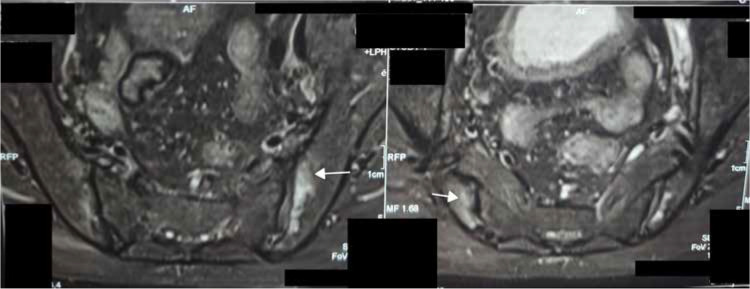

We report the case of a 67-year-old male with a two-year history of inflammatory polyarthritis, fatigue, and low back pain. He also had a history of biopsy proven neutrophilic dermatosis in the past. On admission and examination, he had pallor. Laboratory evaluation showed macrocytic anaemia, elevated erythrocyte sedimentation rate (ESR), and C-reactive protein (CRP). MRI of Sacroiliac joints showed presence of bilateral sacroiliitis. Bone marrow examination showed the presence of cytoplasmic vacuolisation in myeloid and erythroid precursor cells. Genetic analysis confirmed a diagnosis of VEXAS syndrome. He improved with prednisolone and Sulfasalazine with no further relapse on follow up. This case report highlights the importance of considering VEXAS syndrome in older adults with presentation of spondyloarthritis and macrocytic anaemia. Early diagnosis and treatment with corticosteroids and steroid-sparing agents can lead to significant improvement in symptoms and are important for a good outcome.